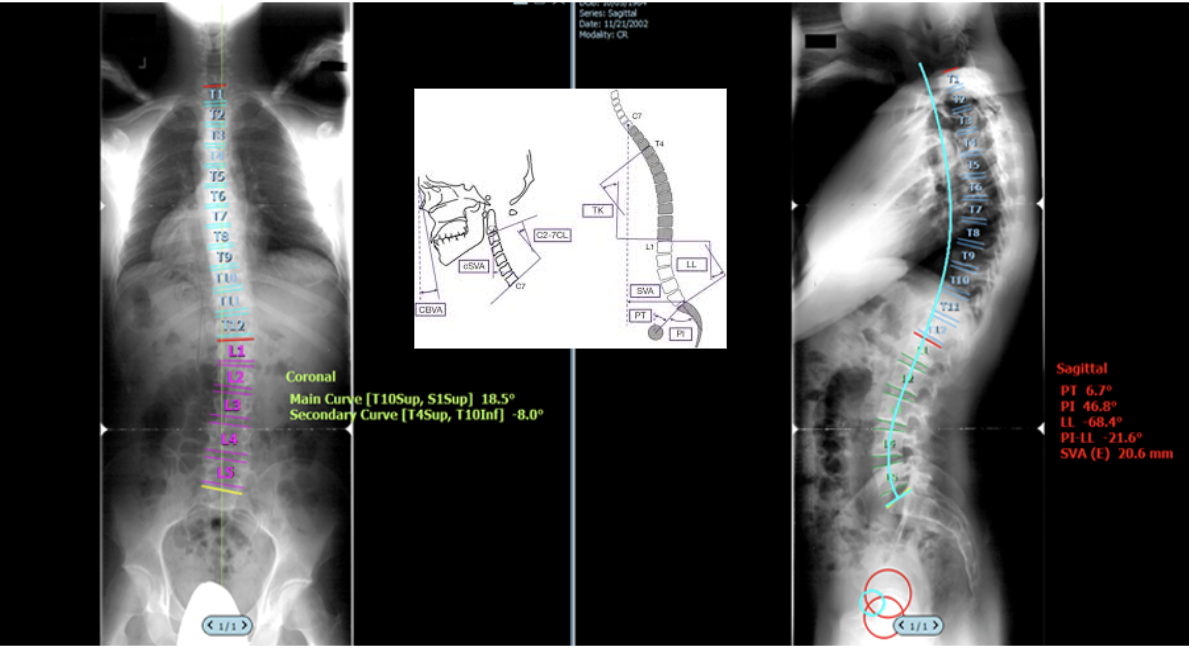

A centralized, easy-to-use resource for spine imaging measurements. Explore step-by-step guides, annotated images, and video tutorials for X-ray, MRI, and CT across the cervical, lumbar, and full-length spine.